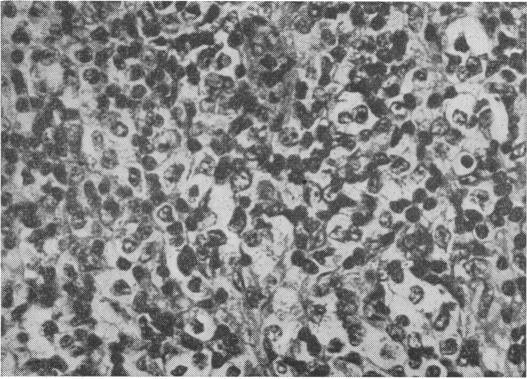

DISSEMINATED HISTOPLASMOSIS FOLLOWING LONG-TERM STEROID THERAPY FOR RETICULOSARCOMA.

Br Med J. 1965 Sep 11;2(5462):631-2. doi: 10.1136/bmj.2.5462.631.